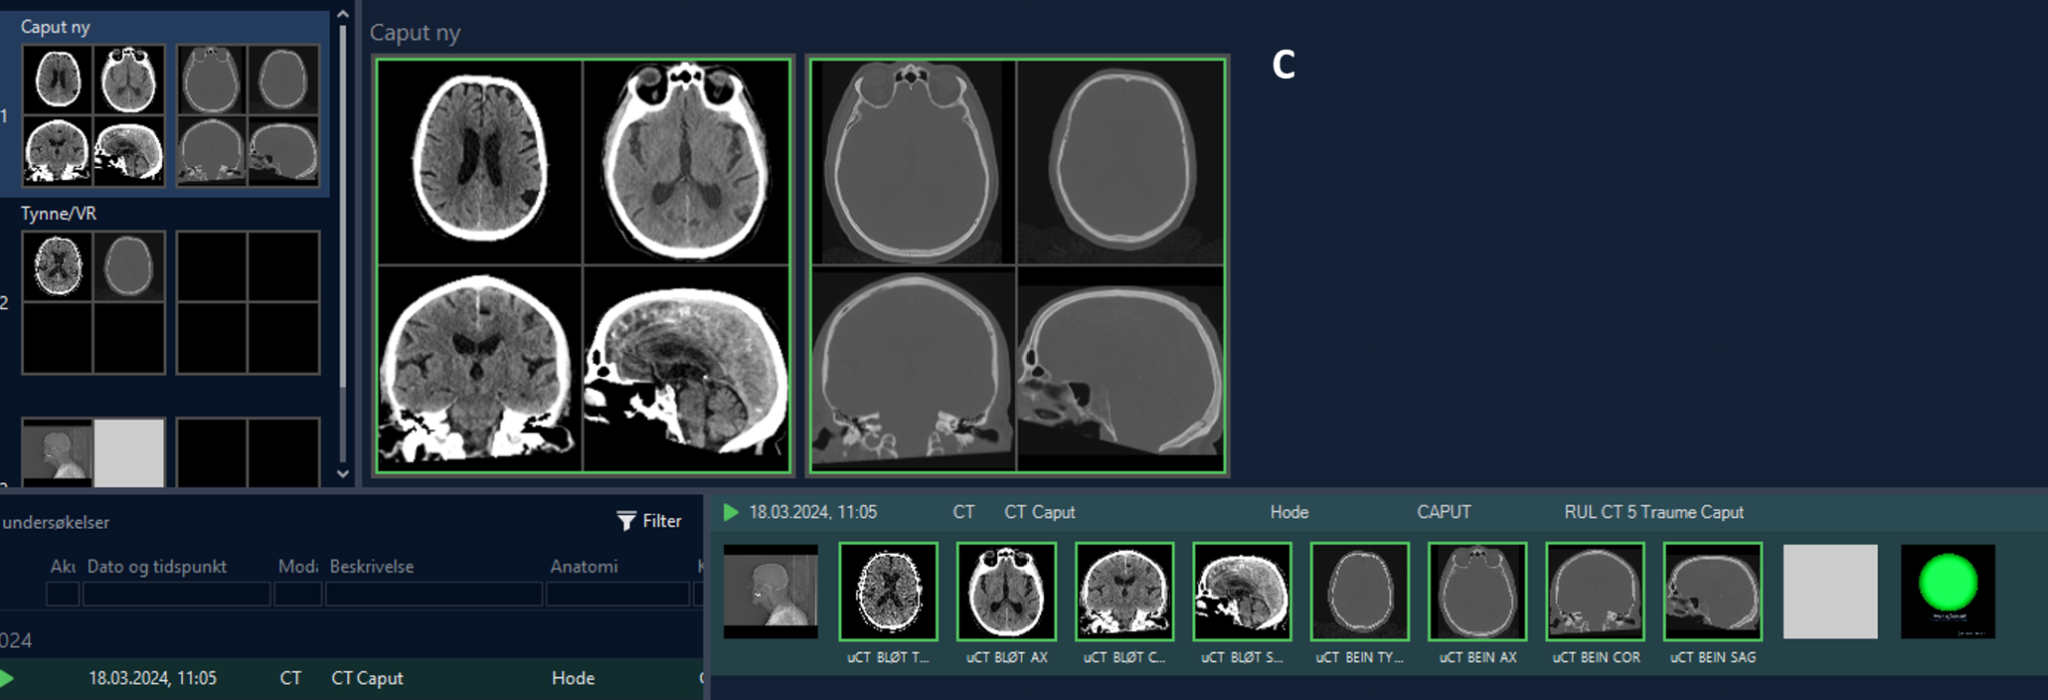

Over a 3 month period (from 1 June to 31 August 2024), all patients with suspected TBI and stroke patients who underwent a head CT were included in this study, and were approved by the regional ethics committee (REK 324897). Radiologists and radiographers from Oslo emergency department and Oslo University hospitals were instructed to “push” images from PACS to the NeoMedSys platform (details below). CT images came from 6 different CT scanners (Simens and GE) and were pushed to NeoMedSys as DICOM files and tagged digitally by the frontline user and processed using the VIOLA-AI model (details below) within NeoMedSys. Results of the analysis were presented as an automated VIOLA-AI report presented back in PACS consisting of a binary mask demarcating the ICH and its volume and a green circle when an ICH was not detected(Figure 1-a).

Demographic data were retrieved, including the time when: 1) CT was performed, and 2) the radiologist signed the report. Two patient groups were created based on whether an ICH was detected or not. Within the ICH detected group the clinician further classified the bleed etiology as being: epidural hematoma (EDH), acute subdural hematoma (ASDH), subarachnoid hemorrhage (SAH), intraparenchymal hematoma (IPH), or intraventricular hematoma (IVH), as well as evidence of mass effect (Figure 1-b). As this was a live consecutive patient population other pathologies were also encountered and were classified as non-ICH with other pathologies i.e., tumor, non-hemorrhagic stroke, etc. All information was retrieved from PACS and the signed radiology report (Figure 1-c).